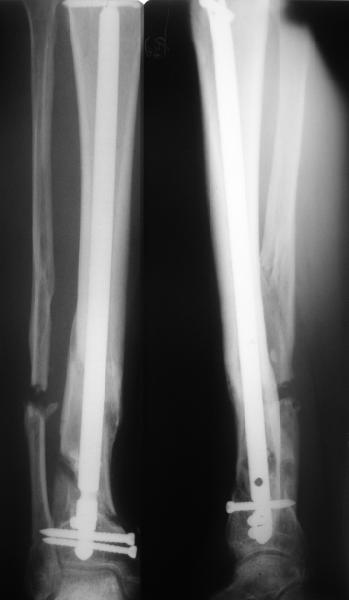

Гвоздь, конечно же, лучше брать с расширенными возможностями

дистального блокирования. Линейка таких гвоздей сейчас представлена

довольно широко различными фирмами. У нас в клинике наиболее часто

используется гвоздь MetaDiaFix-T, выпускаемый на базе гвоздя UTN

предприятием ЦИТО. В данном гвозде дистально раполагается овальное

отверстие, в которое очень удачно вводятся два винта и заклиниваются

между собой, обеспечивая угловую стабильность. Пример использования

такого гвоздя привожу ниже.